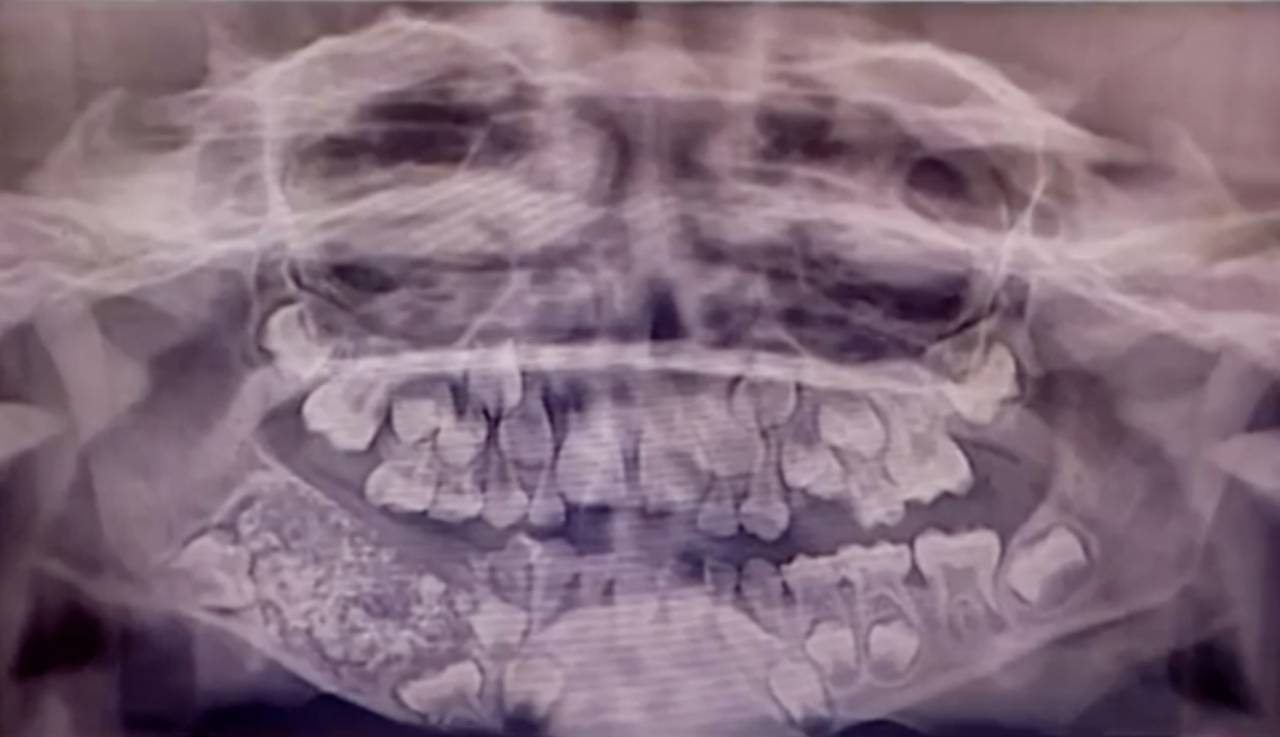

أفاد أطباء إنهم اقتلعوا نحو 526 سن وضرس وناب من فم طفل عمره سبع سنوات أمس (الأربعاء)، والذي يعاني من حالة طبية غير عادية. ويعاني الطفل من ورم في الجانب الأيمن من الفك السفلي له منذ كان عمره ثلاث سنوات.

وأظهر فحص طبي أجراه جراحون وجود نمو كبير يحتوي على هياكل صلبة متعددة في الفك. وقال الأطباء إن هذه حالة طبية فريدة من نوعها. ووصفت الحالة النادرة بأنها «ورم مركب بالأسنان». وفي 2014 اقتُلعت 232 سناً من فم مراهق في مومباي بالهند أيضا.